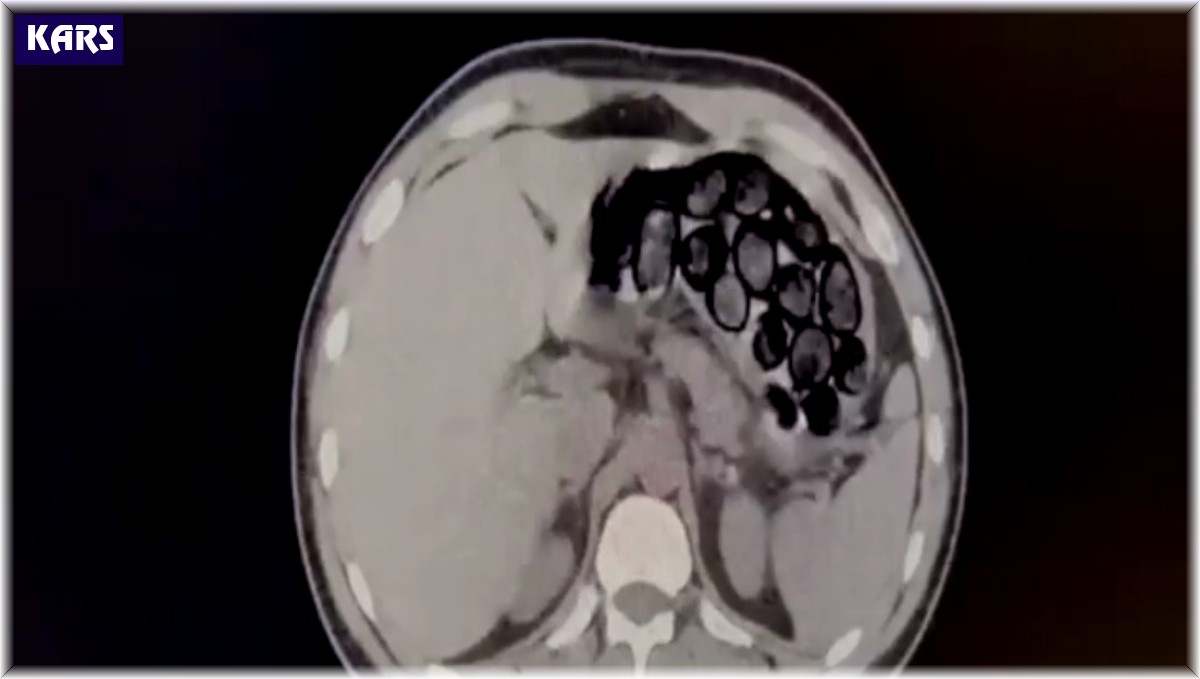

Jandarma ekiplerince takibe alınan İranlı şahıs ve beraberindeki 2 kişi, Kars'ın Selim ilçesi girişinde ticari takside yakalandı. Yapılan üst aramasında bir şey bulunamayan Omid Baghernezad, Kars Harakani Devlet Hastanesi'ne götürüldü. Burada çekilen röntgende Omid Baghernezad'ın mide ve bağırsağında kapsüller halinde 65 parça halinde 412 gram sentetik uyuşturucu olduğu belirlendi.